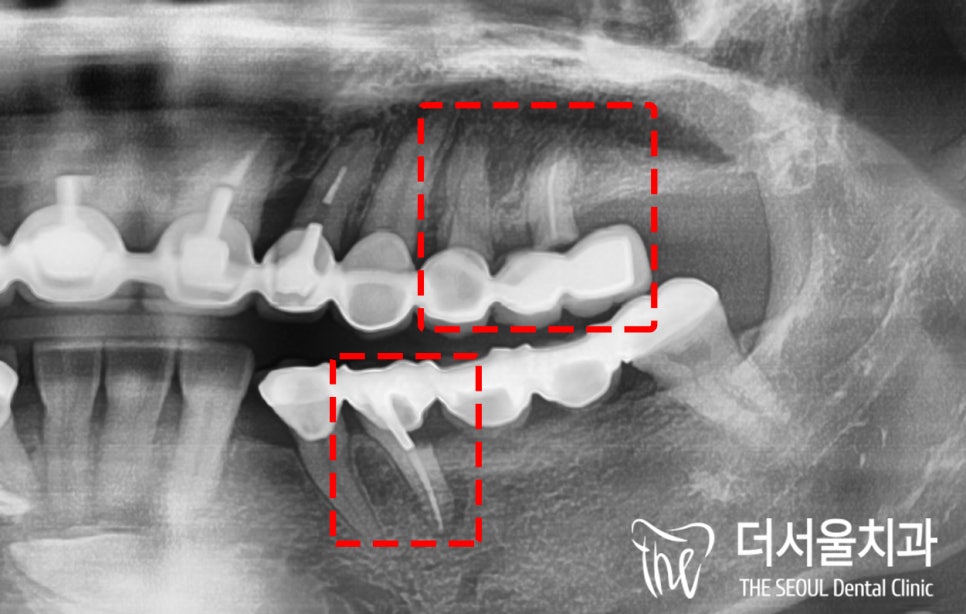

우선 왼쪽 어금니 부근을 살펴봤는데요

오래된 보철 씌워져 있는 것 말고는

별다른 문제들은 발견되지 않았습니다.

그러나 파노라마 사진을 통해 알 수 있었죠.

겉으로는 문제가 없던 곳도

안을 살펴보면 그게 아니라는 것을…

오래된 보철 하방으로 나타난 병소가

해당 치아는 물론이며 주변 치조골,

치근까지 괴롭히고 있었습니다.

염증이 군데군데 퍼져있어

치조골 소실은 물론이며

극심한 통증까지 이어지게 된 것이죠.

보철을 탈거하고 살펴봤더니

생각보다 더 심각했습니다..